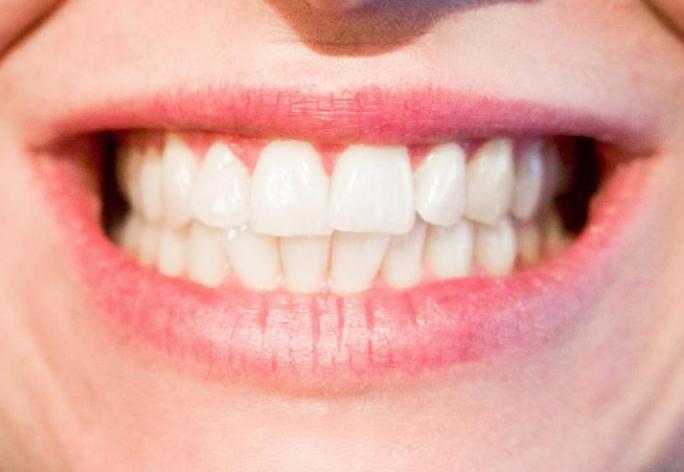

一、牙齿的外源性着色。

*进入口腔的外来色素或口腔中细菌产生的色素沉积在牙面称为牙齿外源性着色。

通俗的说,外源性着色就是因为口腔卫生不良,抽烟熏得,长期喝茶、喝咖啡、喝中药、嚼槟榔等行为导致的牙齿表面,特别是舌面出现的刷不掉的褐色或黑褐色色素沉着。

注:长期用氯己啶(洗必泰)或高锰酸钾溶液漱口或用药物牙膏,如洗必泰牙膏可在牙面形成浅褐或深褐色着色;牙齿局部氨硝酸银浸镀治疗后,相应部位也会变成黑色。